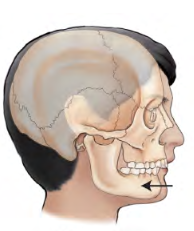

Retraction

movement backward or the condition of being drawn bac k.